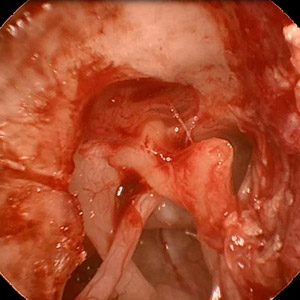

Endoskopischer Blick ins Epitympanon